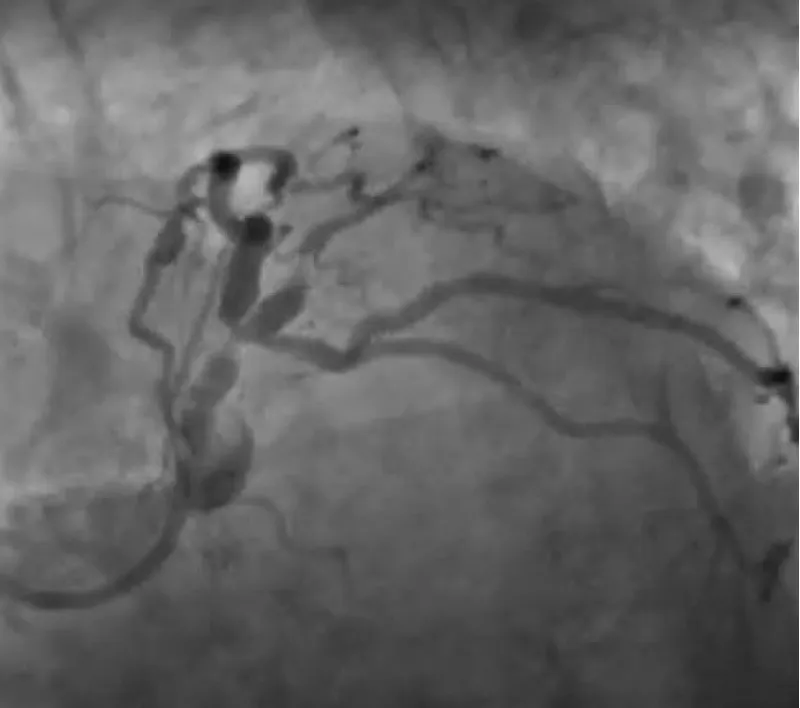

With the support of deep sedation, an angio-guided right femoral access was obtained, and a 12F introducer was advanced. We crossed the aortic valve with an Amplatzer left 1 catheter with a 0.035” wire and exchanged the wire with an extra-stiff Safari. We performed aortic Valvuloplasty with a Nucleus balloon 18 x 40 mm. (Figure 7) Then, we exchanged the wire and advanced an IMPELLA CP device, starting a protected PCI on LM. (Figure 8) An EBU 4.0 catheter was advanced, the stenosis was crossed on the Left Main (LM) and mid-Left Anterior Descending artery (LAD) using a BMW guide wire, and with the aid of a microcatheter a 0.014” Rotawire was positioned, followed by rotational atherectomy using a 1.5 mm burr on LM and mid LAD, (Figure 9) and a 2.0 mm burr on LM alone (Figure 10). This was followed by predilation with a 2.5 x 20 mm SC balloon and the implantation of a 2.5 x 32 mm Synergy drug-eluting stent (Figure 11). Then, the Left Main was predilated with a 3.5 x 12 mm NC balloon, and a 4.0 x 15 mm Xience Sierra drug-eluting stent was implanted and post-dilated with a 4.5 x 8 mm SC balloon (Figure 12). Immediate angiographic control confirmed a successful result. Then we removed the IMPELLA CP device and advanced a 14F e-sheath Edwards on the right femoral artery, crossed the aortic valve with a Safari extra-stiff wire, and performed a Sapien 3 23 mm valve implantation with a good angiographic result (Figure 13). Post-procedural echocardiographic and angiographic assessment confirmed the valve was correctly positioned, with no significant gradient and a minimal residual leak. The procedure was uneventful, and the patient was discharged on the fourth day with triple therapy: Aspirin 100 mg once daily, Clopidogrel 75 mg once daily, and Apixaban 2.5 mg twice daily. At the quarterly follow-up, the patient reported hospitalization for anemia, requiring a transfusion of 3 units of packed red blood cells. Endoscopic exams were negative, and hypochromic, normocytic anemia persisted. Given the patient’s CHA2D2-VASc score of 5, HAS-BLED score of 4, and recent dual Drug-Eluting Stent (DES) implantation, she was admitted for left atrial appendage percutaneous closure. Before this procedure, a repeat coronary angiography showed good results in the previously implanted stents (Figure 14). Subsequently, through a right femoral percutaneous approach using a 12F introducer, a 22 mm Amulet device was positioned for left atrial appendage closure (Figure 15). The procedure was completed without complications. At the 4-year follow-up, the patient presented in good hemodynamic status, with an echocardiographic ejection fraction of 55%. She continued on clopidogrel 75 mg once daily therapy.

Figure 8: Impella CP Device.